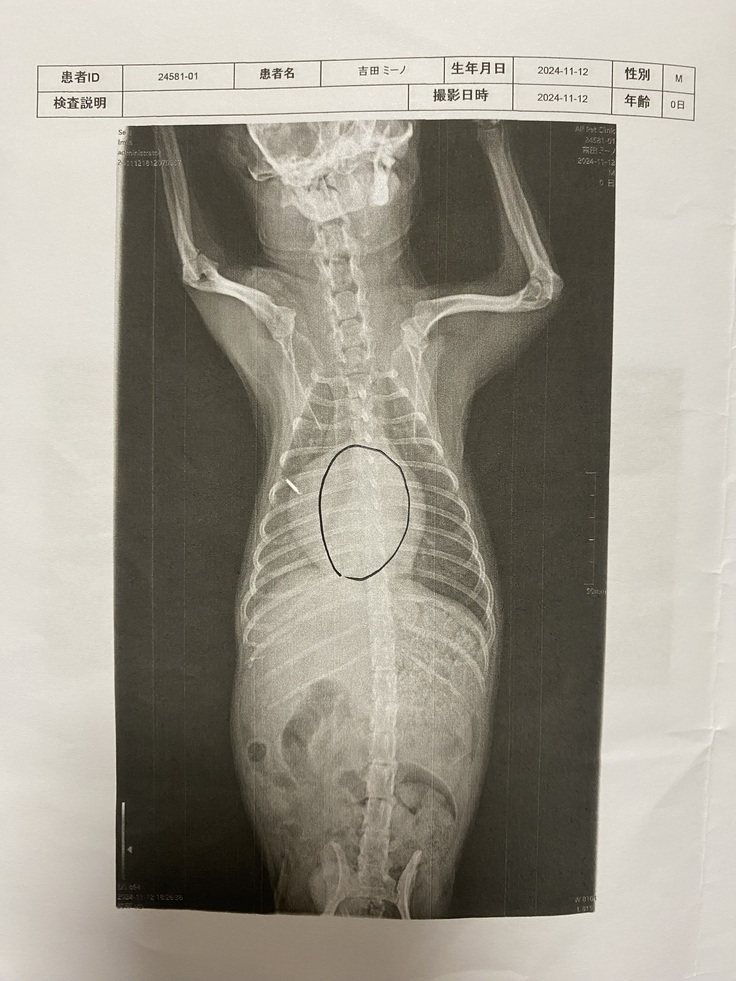

↑病院で撮影してもらったレントゲン画像。

心臓が通常の3倍にも膨れあがり、肺を圧迫していました。